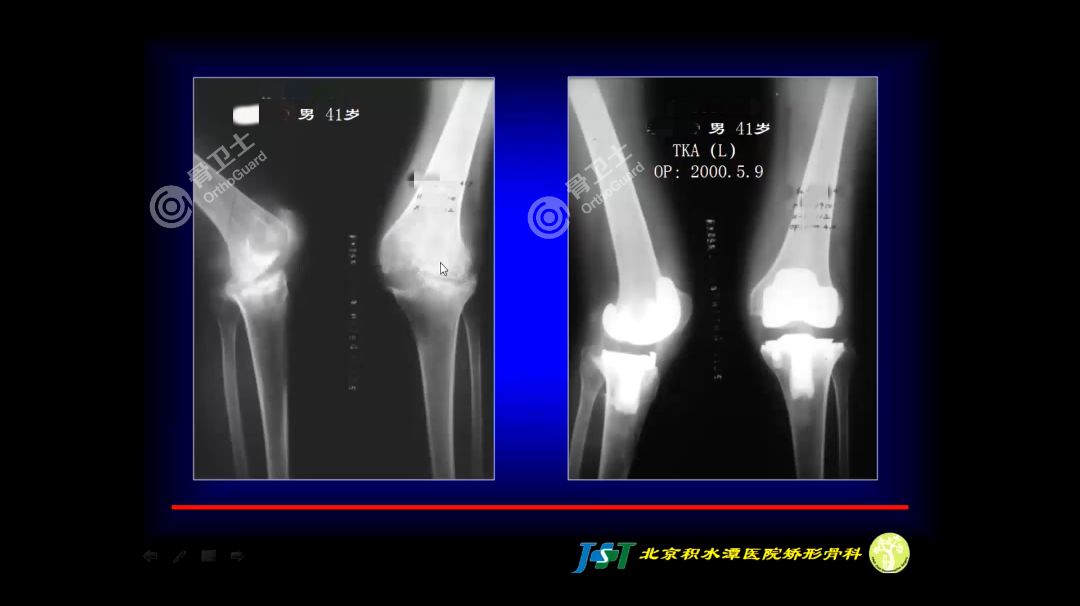

本次专家培训会,周乙雄教授通过六个疑难病例的深入讲解,将从医50多年积累的经验与骨科同道分享。小骨从中选取两个病例进行分享展示,完整培训内容将上传至骨卫士官网及公众号。周乙雄教授介绍,该患者为类风湿性关节炎,于2000年进行髋、膝关节置换术。由影像资料可以看出,患者骨盆和股骨端骨质不好,骨密度低,考虑到置换后的稳定性,决定使用骨水泥型假体,比较牢靠。周乙雄教授介绍,骨水泥搅拌时发生的气泡是导致骨水泥型假体不牢靠的原因,产生气泡的地方容易发生骨水泥断裂,导致假体发生松动。该患者采用的是第三代骨水泥技术,其搅拌是在密闭容器中真空搅拌,避免空气在搅拌时进入骨水泥产生气泡,使假体更加稳定。周乙雄教授指出,在注入骨水泥时一定要加压,将加压器伸到股骨的顶端,加压注入骨水泥。此外,第三代骨水泥技术还有其他的一些要求。周乙雄教授指出,相关文献资料显示,骨水泥型假体发生松动大多为髋臼松动。髋臼是一个特殊的结构,是由髂、耻、坐骨的延续形成髋臼,髋臼的骨质厚度不同,在打磨髋臼时要注意,既不能影响髋臼的包合性,又要达到一定深度,露出一些松质骨,这样加压注入骨水泥的时候才能到达骨小梁微小的结构中去,让假体更加牢靠,避免发生松动。周乙雄教授指出,由影像资料可以看出,该患者膝关节是很典型的类风湿性关节炎。类风湿性关节炎的病变主要在滑膜,滑膜附着在膝关节的软骨和滑膜翻转的地方,蚕食膝关节的软骨,导致膝关节内侧软骨缺损严重。周乙雄教授强调,类风湿性关节炎患者在术后发生感染的几率较高,在做类风湿性关节炎的滑膜切除和关节置换的时候,术中一定要严格执行无菌操作,最大限度降低术后感染的发生几率;在术后,也要定时检查血沉、C反应蛋白,了解是否发生感染的情况。周乙雄教授指出,该患者骨密度低,骨质不好,在截骨和安装关节假体的时候要非常小心,动作轻柔,避免发生医源性骨折。周乙雄教授认为,是否进行关节置换,年龄不是决定因素,而是要从患者的实际需求、功能恢复的角度出发,综合判断。因此,医生和研发人员要不断努力,提高技术,完善假体设计,不断延长人工关节的使用寿命,减少翻修次数,让患者最大限度获益。